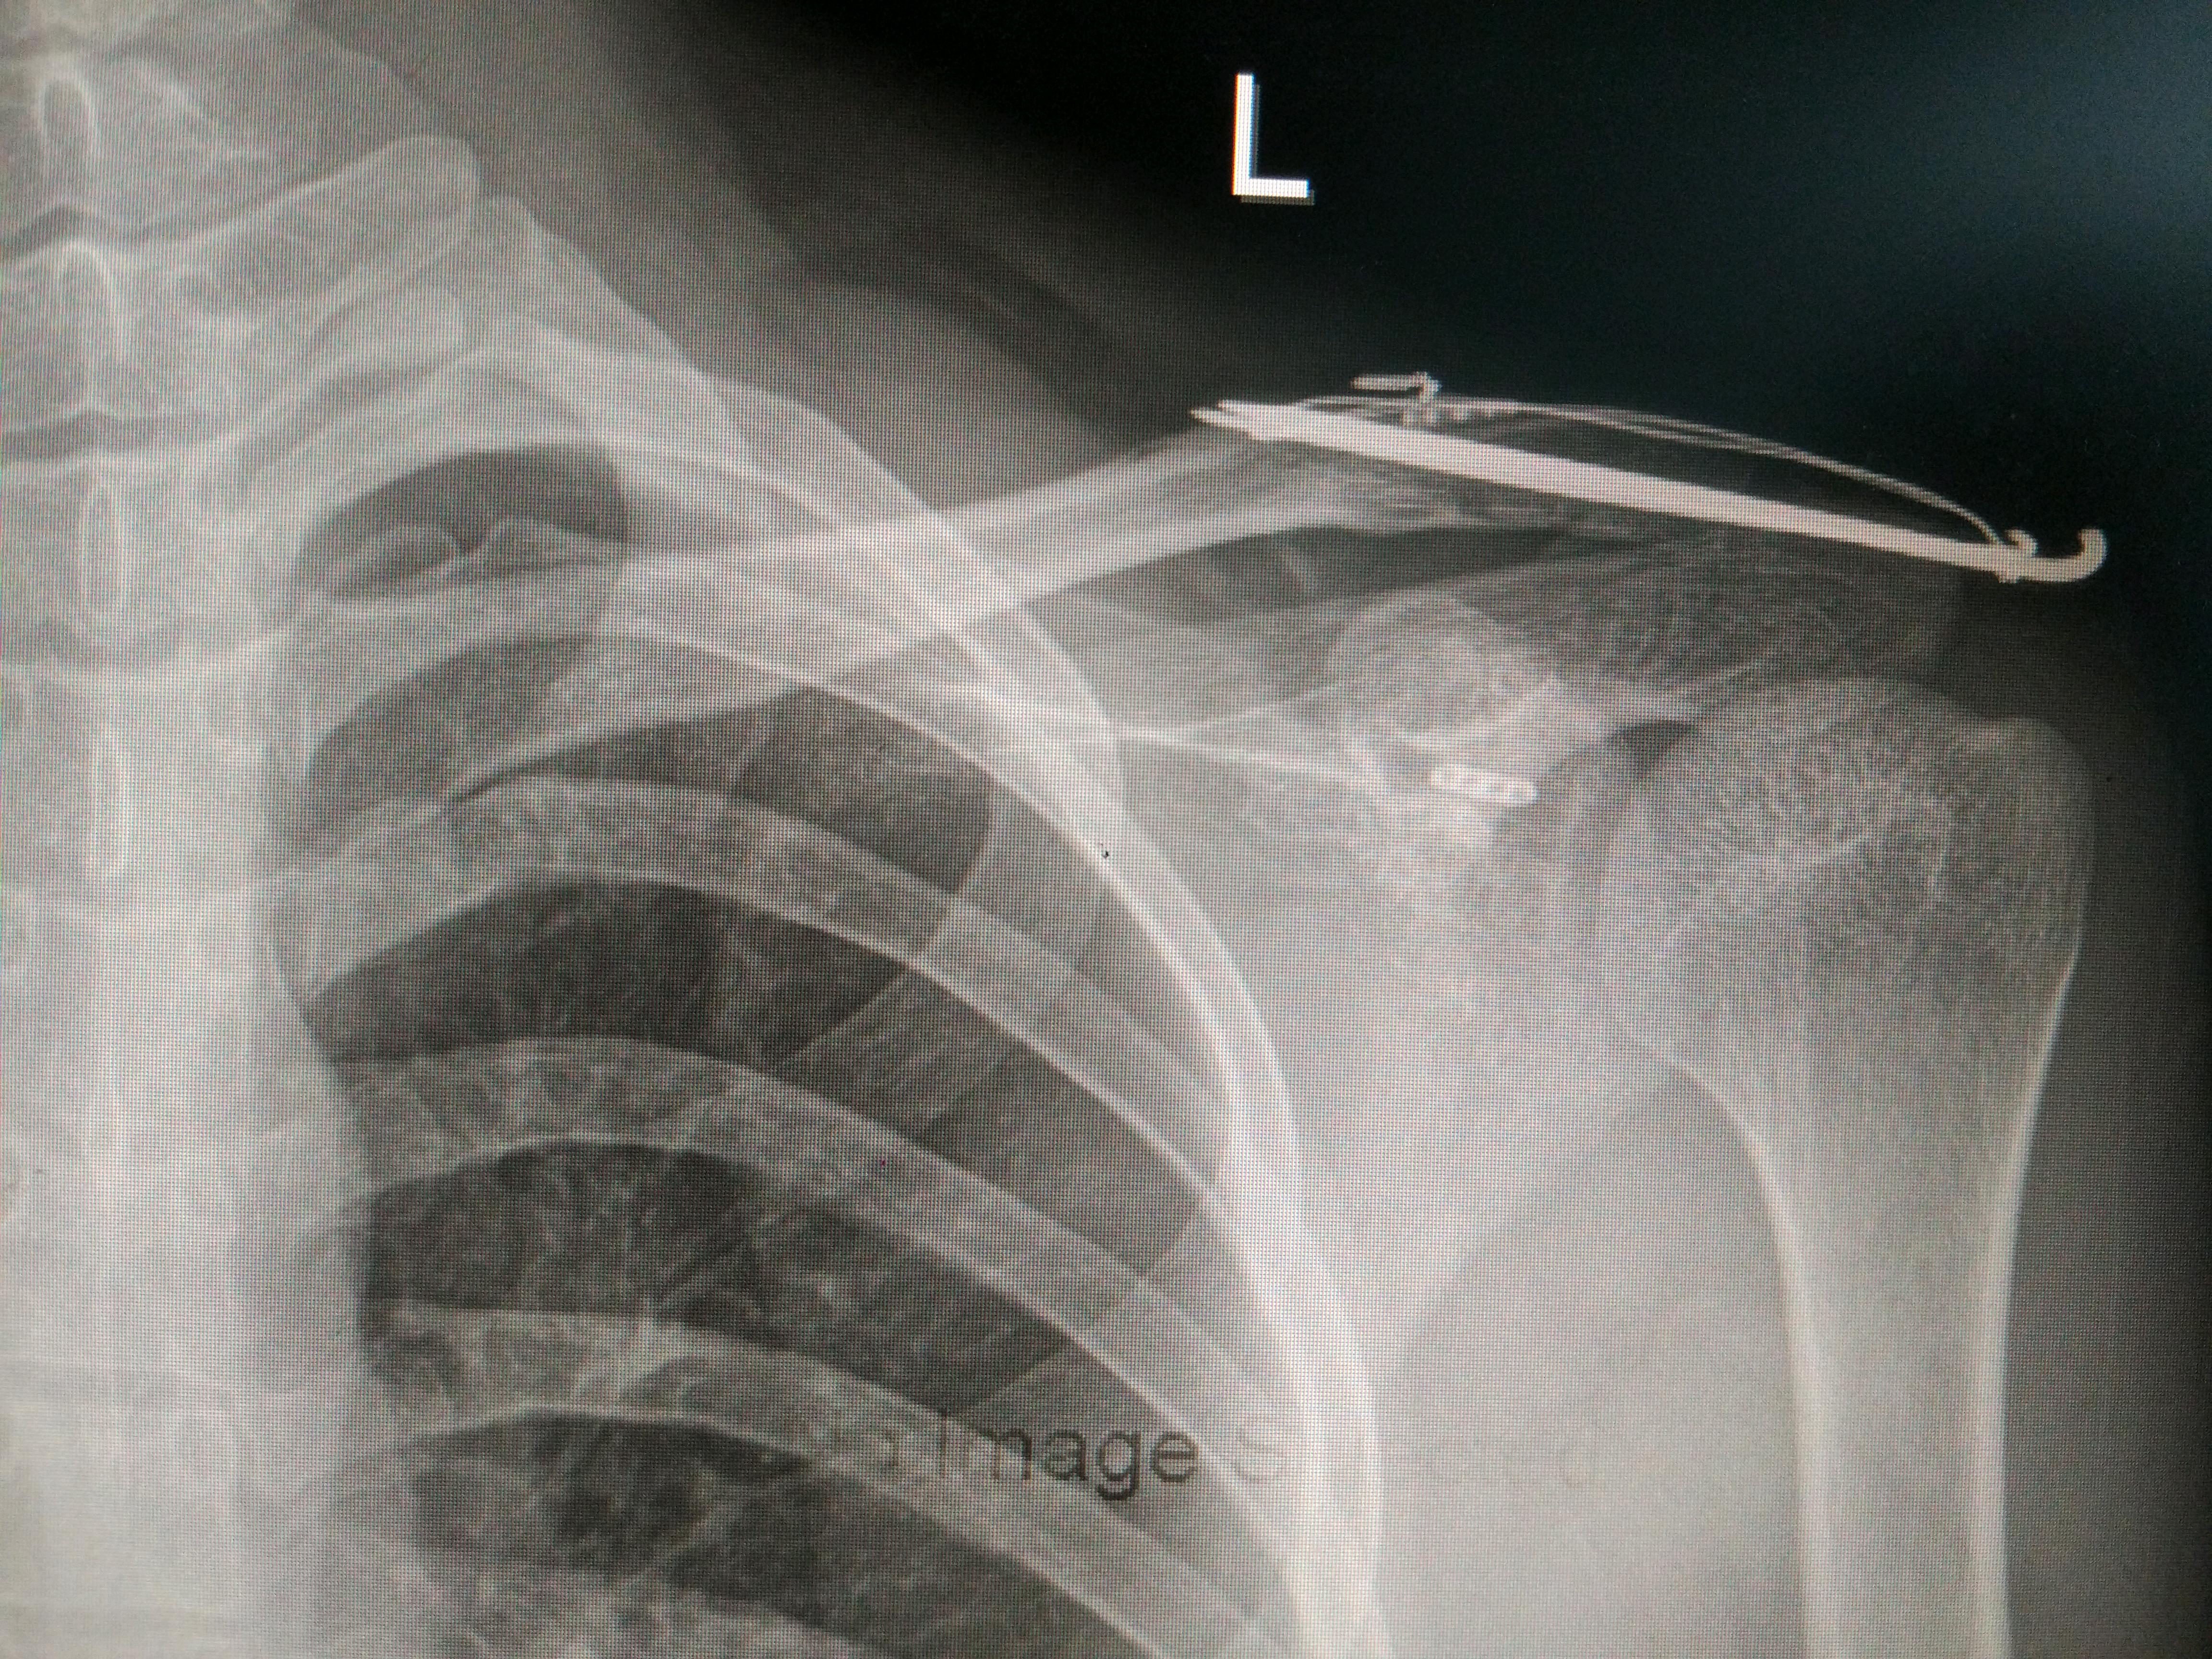

锁骨骨折吧

老哥们,术后三个月,长好了没?医生说术后六个月拆除,这三个月总感觉浑身难受。

我的是钢板加螺钉内固定,你这和我不一样!

我这个很少见吗?[黑线][黑线][黑线]

克氏针

自己骨折也有点会看片子了,好像恢复不错,骨折在哪里看不清

看不出骨折在哪里岂不是[滑稽]………还是听医生的话吧,再难受三个月估计会好

这个可以拆了,已经六个月了,很开心

拆了一个多月了,身体还是没以前舒服[泪]

拆了三个多月了,还是没以前舒服[泪]

拆了10个月,还是没以前舒服